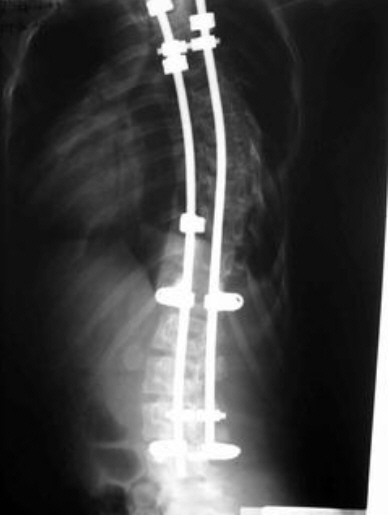

新华网消息:5月31日,北京协和医院脊柱外科沈建雄教授做客新华访谈,就青少年脊柱侧弯的治疗与预防与网友在线交流。以下是沈教授治疗脊柱侧弯典型病例资料图。

12岁女孩脊柱侧弯(术后即时效果X光片 资料图)